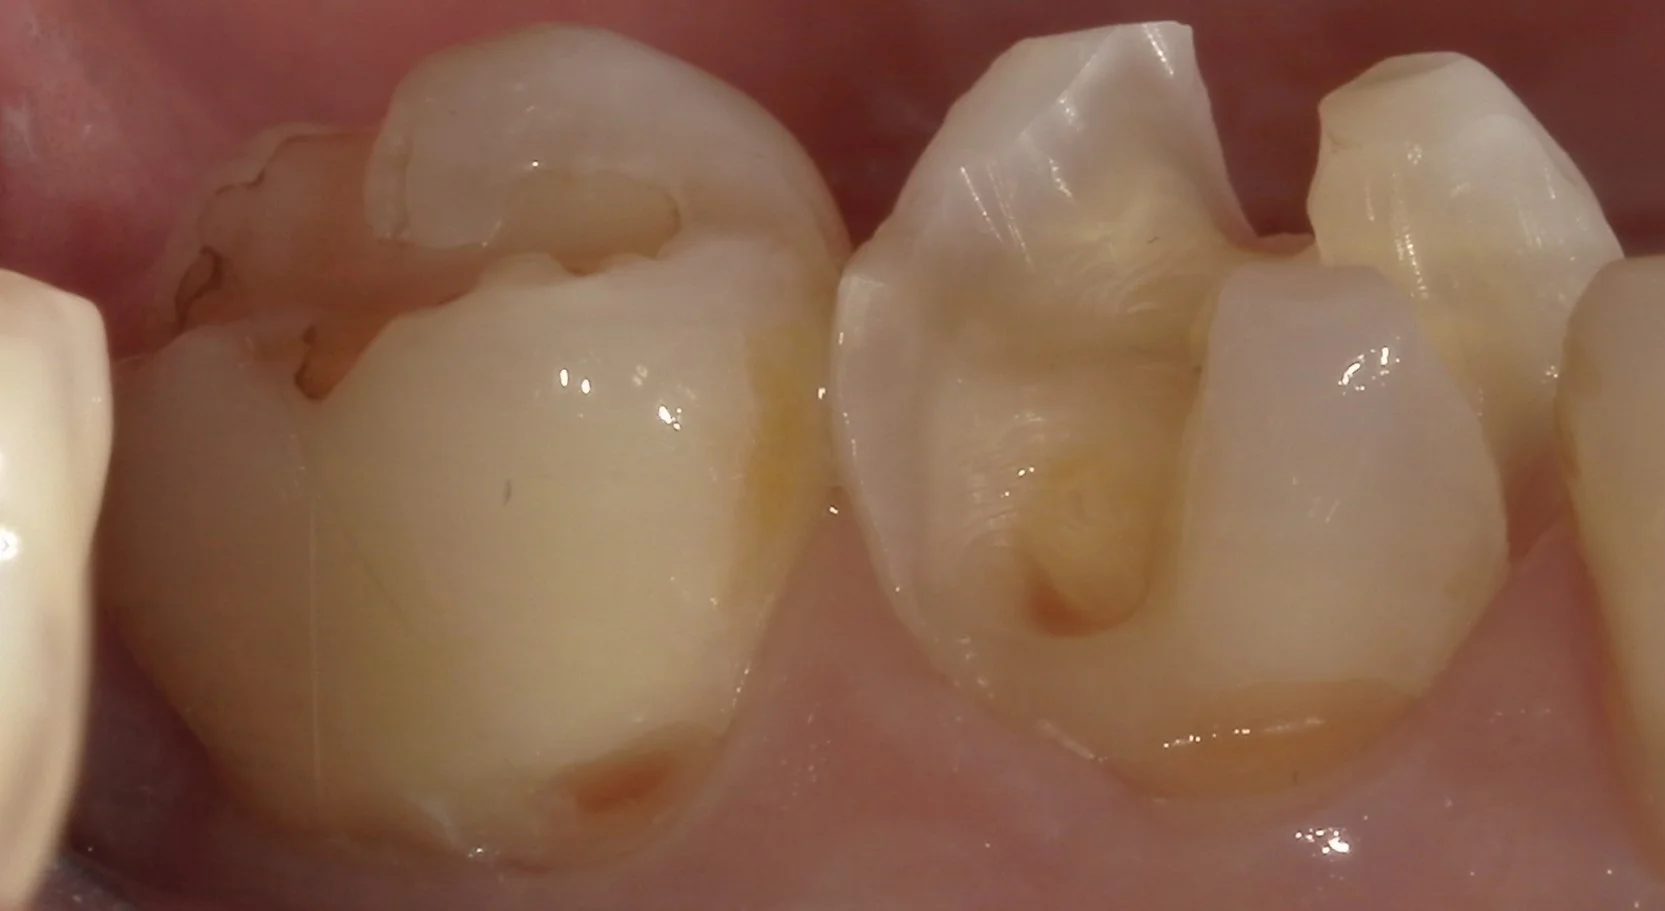

続いて、側面からの写真になります。

歯の側面も同時に治療したケース。|坂寄歯科医院(取手市藤代) - 画像4

そして、最後、詰め終わって噛み合わせの調整・研磨まで終了したのがこちらになります。

まず、噛む面です。

続いて、側面。

歯の側面も同時に治療したケース。|坂寄歯科医院(取手市藤代) - 画像6

歯の形態が違和感なく自然に仕上げられたかと思います。

随分とご自身の歯を失っていましたが、無事に残っている歯も亀裂が入ることなく詰め終わることが出来ました。

この処置後、また別の処置で来院された際に症状について聞いてみましたが、何の問題もなく生活出来ているようで良かったです。